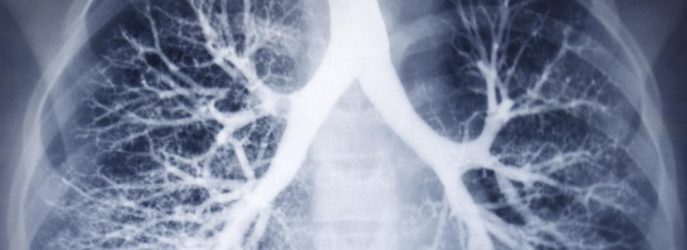

Innovations en Pneumologie, Que retenir de 2015 ?

Voici une liste non exhaustive par secteur d’activités, concernent tant les aspects physiopathologiques, notamment dans le syndrome des apnées du sommeil, que diagnostiques ou curatifs. Pour les premiers, citons les nouvelles valeurs de référence en spirométrie, l’apport des cryobiopsies dans les pathologies interstitielles diffuses, l’évaluation des bronchectasies de l’adulte, …...